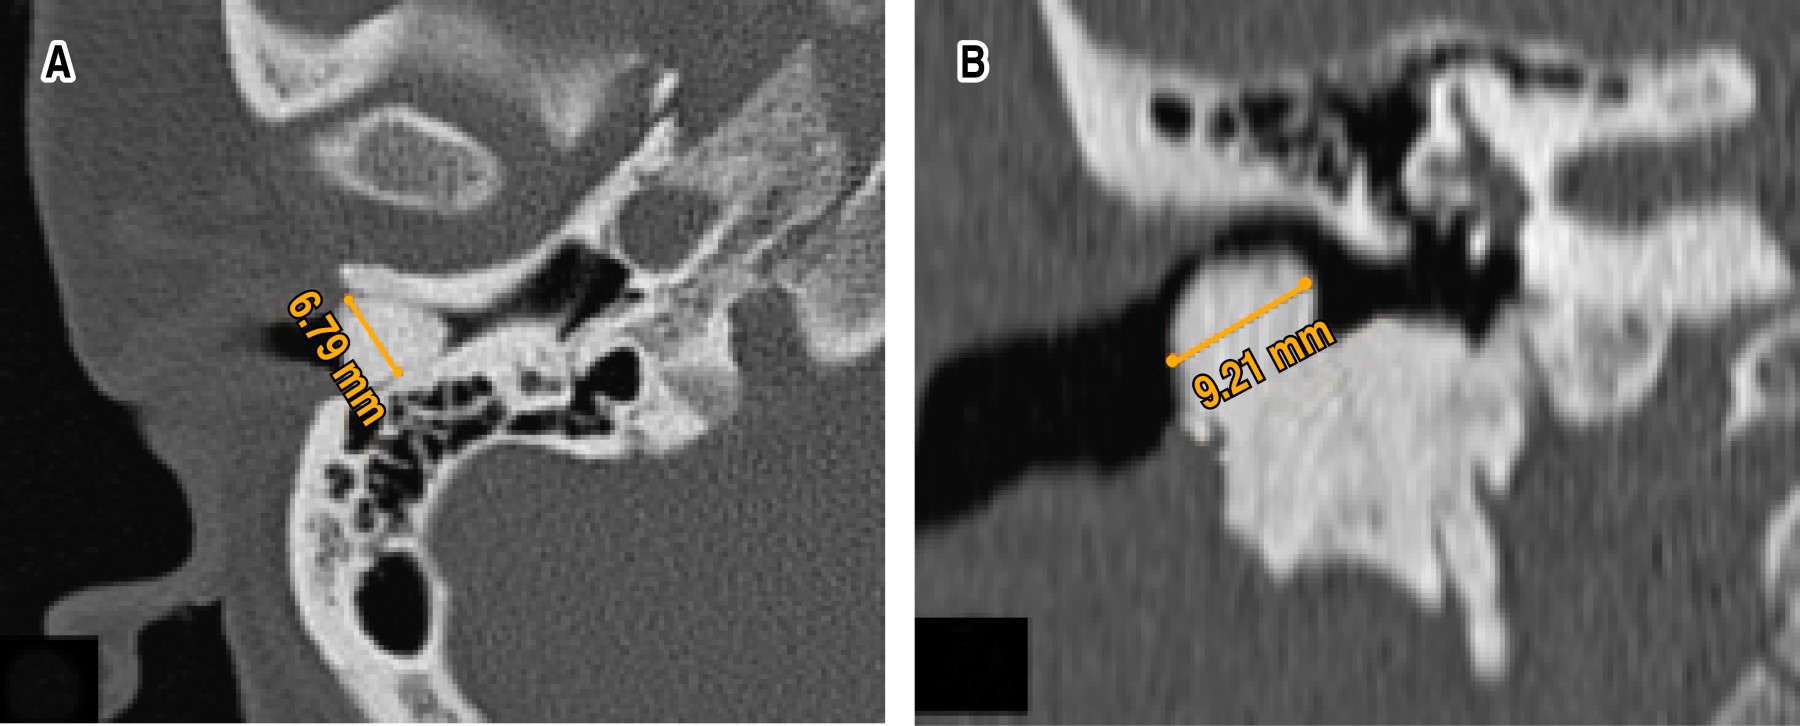

External auditory canal osteoma

Osteomas of the external auditory canal are benign tumors of bone tissue, slow growing, unilateral and initially asymptomatic so there are no real data on their incidence and frequency. The location of the osteomas is lateral to the isthmus of the external auditory canal and originate from pre-bone connective tissue located in the tympanosquamous or tympanomastoid sutures. The most common complication of osteoma is the formation of cholesteatoma and erosion of the duct walls. Treatment depends on the size of the lesion, and it can be conservative or surgical. We present a case of a 30-year-old female with an osteoma in the right external auditory canal diagnosed and treated at the Mexican Institute of Otology and Neurotology of Mexico City and a literature review of case reports and case series with this pathology published until April 2021.

Figure 1